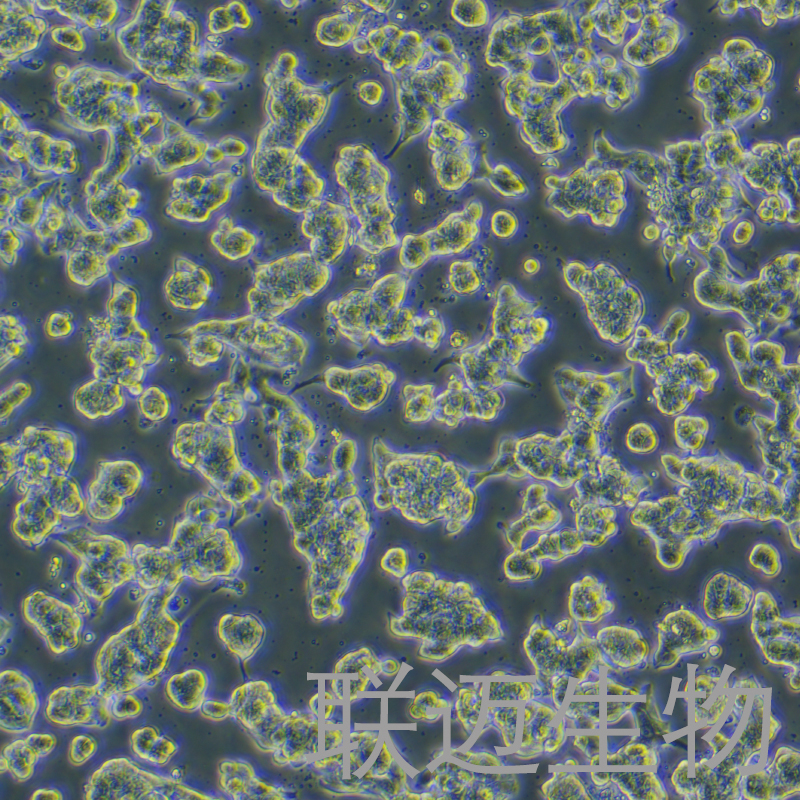

细胞形态:

上皮细胞样

生长状态:

贴壁生长

细胞形态

背景简介

SNU-719细胞来自韩国53岁男性原发性腺癌患者的胃组织。使用光学和电子显微镜进行形态学研究,通过放射免疫测定法测定上清液和细胞裂解物中的CEA,α FP和CA 19-9和TPA。筛选p53和c-Ki-ras基因突变并通过测序确认。来源于中等分化的肿瘤的细胞系以弥漫性单层形式生长,而来自分化差和最小纤维增生的肿瘤的细胞系仅作为非贴壁生长。SNU-719细胞系在细胞裂解物和上清液中均具有高浓度的TPA,p6突变(75%)。使用限制性核酸内切酶HinfI和多态性DNA探针ChdTC-15和ChdTC-114的DNA图谱显示出不同的独特模式;这表明这些细胞系是独特的,没有交叉污染。我们相信新表征的胃癌细胞系将为人类胃癌相关研究提供有用的体外模型。